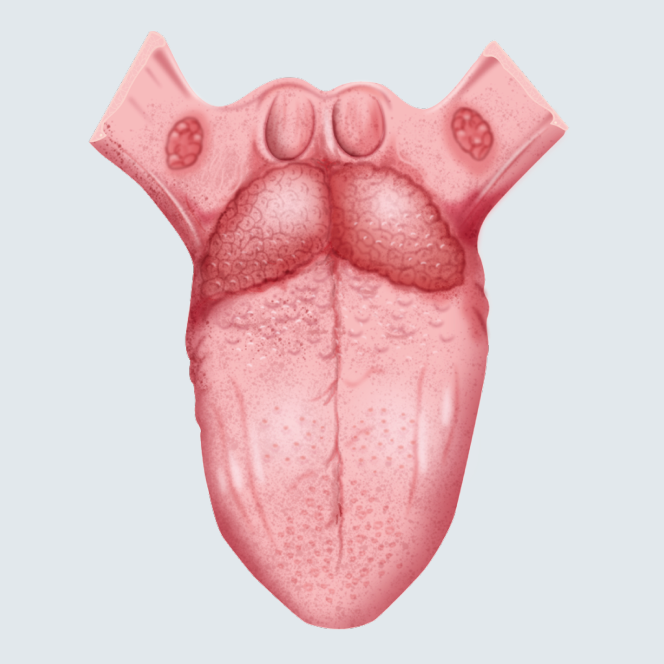

Lenguas